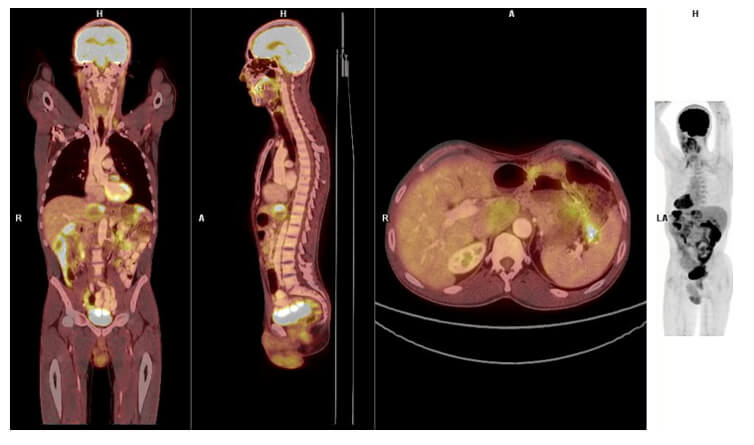

PET CT

A PET/CT combines the nuclear medicine sensitivity with the anatomical location of the CT scanner.